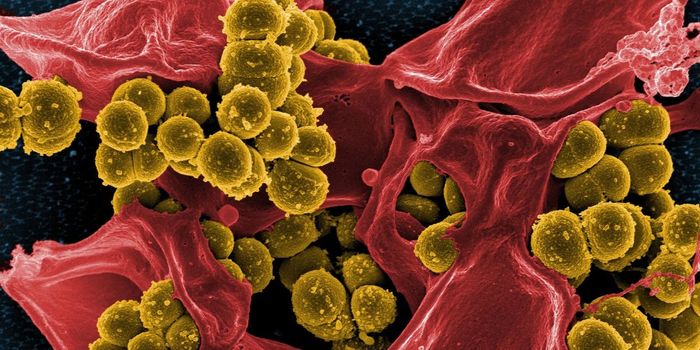

JUN 08, 2018MicrobiologyThe S. aureus pathogen doesn't only invade bone, it uses it as a snack.

AUG 20, 2016Clinical & Molecular DXCan the staph superbug, also known as MRSA, be brought down by salt? Scientists finally expose a key weakness in these b ...

MAR 11, 2015MicrobiologyHouseholds can serve as a reservoir for transmitting methicillin-resistant Staphylococcus aureus (MRSA), according to a ...